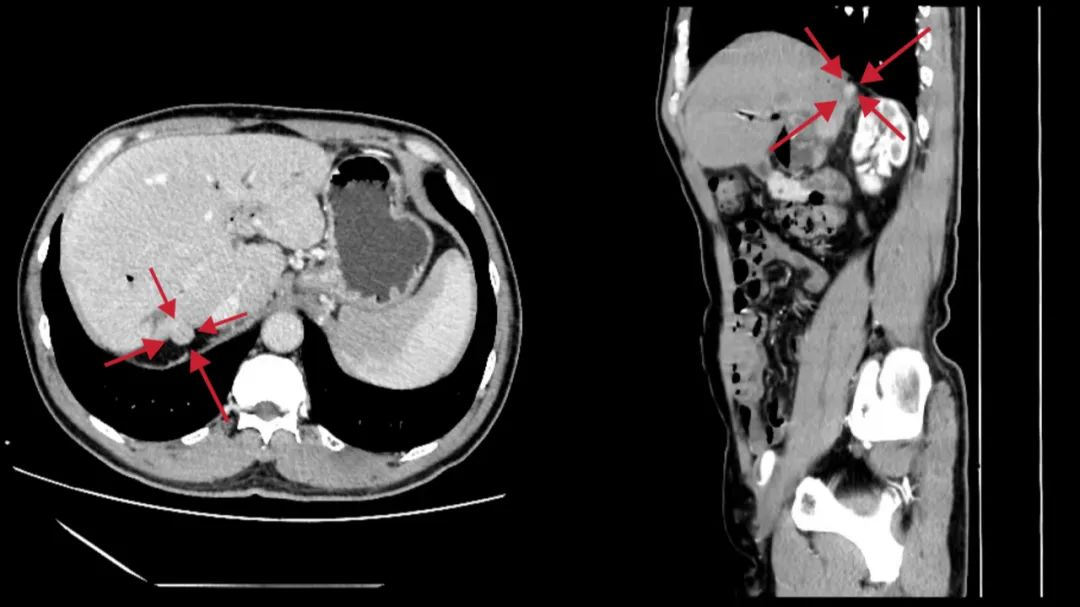

术前的影像学定位

该患者是一名中年男性,体检时发现肝右后叶S7段有一个直径约1cm的肿瘤,增强CT及核磁共振显示肿瘤距离肝右静脉很近。完成术前相关检查后,经院内多学科会诊讨论,认为虽然肿瘤不大,但位置特殊,常规的腹腔镜手术入路显露及操作困难;而传统的开腹手术虽然可以切除肿瘤,但手术切口及创伤会巨大;考虑到肿瘤的位置靠近后腹膜,经我院MDT团队的仔细论证,为患者制定了经右侧腰部后腹膜入路的腹腔镜下肝肿瘤切除手的个体化手术方案。经过充足的准备后,由侯宝华教授主刀,在泌尿外科毕学成主任团队的紧密配合下,顺利地为患者实施了肿瘤切除手术,全程几乎没有出血。术后患者恢复非常顺利。与开腹手术相比,该手术仅在患者右侧腰部留下几个直径0.5cm的小切口,效果非常好。